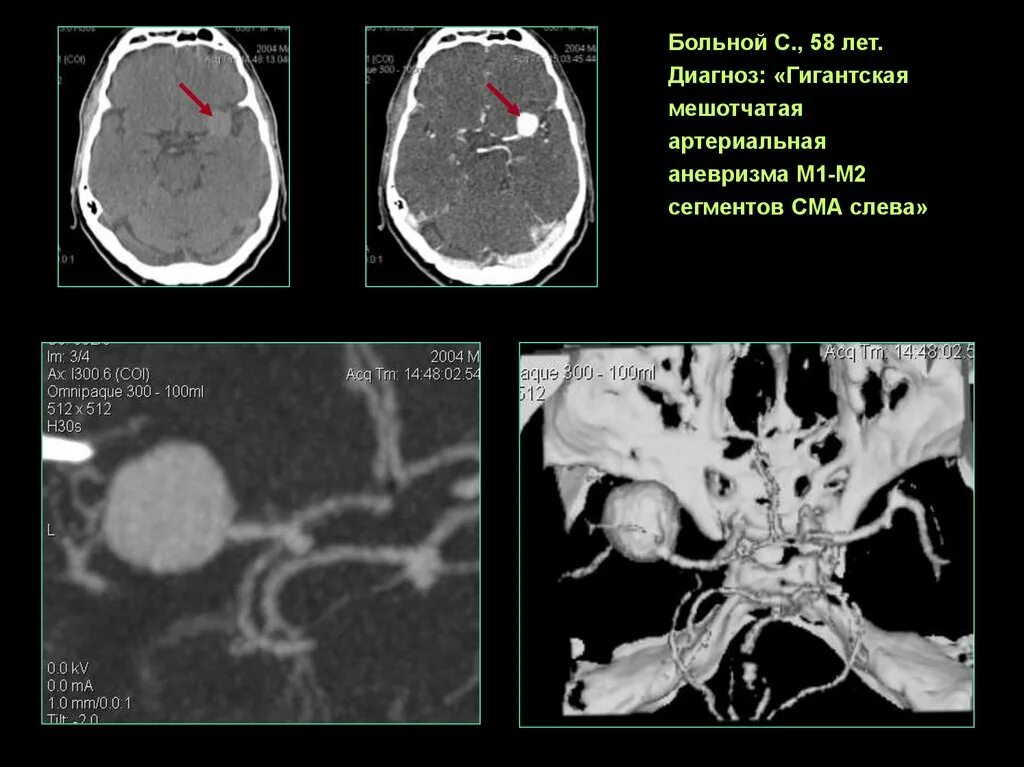

Мешотчатая аневризма внутренней